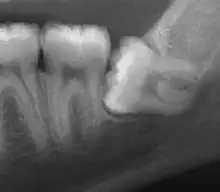

Impacted wisdom tooth with a horizontal orientation | |

An ectopic tooth, also known as an impacted tooth, is a tooth that develops in an abnormal position and fails to erupt into its normal location in the oral cavity. [1] [2] Ectopic teeth can cause a variety of symptoms, such as pain, swelling, and infection, and they can lead to more serious complications if left untreated.

Ectopic teeth may commonly occur within the dentate region of the jaws. Other common sites for ectopic teeth include the maxillary sinus, the nasal cavity, the mandibular condyle, and the palate.[3] The cause of ectopic teeth is not always clear, but it may be related to genetic factors or developmental abnormalities.[4]

Diagnosis of ectopic teeth typically involves a comprehensive dental examination, including X-rays and other imaging tests. Treatment options for ectopic teeth depend on the location and severity of the condition, as well as the age and overall health of the patient. In some cases, observation and monitoring may be sufficient, while in other cases, surgical intervention may be necessary to remove the ectopic tooth and prevent further complications.[5]